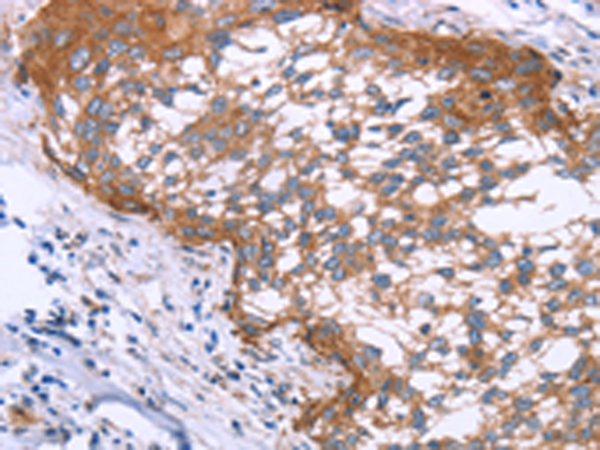

分类: 科研抗体货号: P10658别名: CD246, NBLST3应用: IHC反应种属: Human, Mouse